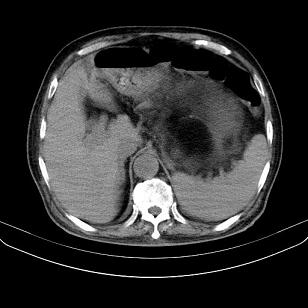

标题: CT21671:男,88岁,左上腹包块 [打印本页]

标题: CT21671:男,88岁,左上腹包块

患者因咳嗽而住院,自觉右上腹包块,无其他不适。

腹膜后高分化脂肪肉瘤

腹膜后脂肪肉瘤

腹膜生占位性病变,脂肪肉瘤可能。

脂肪肉瘤,应测ct值。

支持;后腹膜脂肪肉瘤诊断。

另肠腔扩张及液平,肠梗阻?

左侧腹膜后脂肪肉瘤。